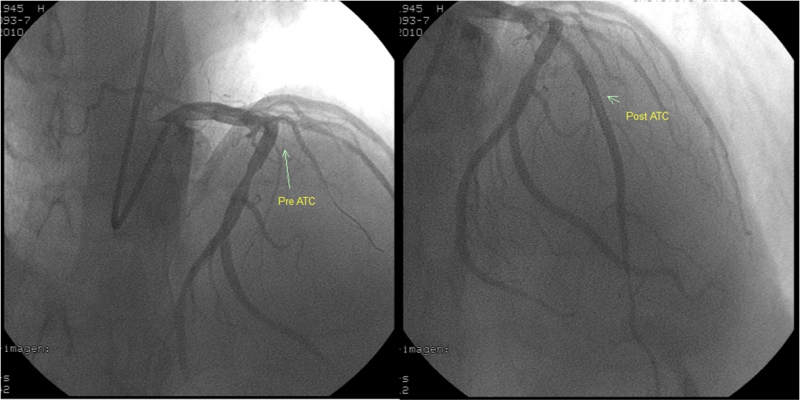

Con este resultado, el paciente es enviado a sala de hemodinamia donde se le realiza CACG de urgencia que muestra oclusión de arteria descendente anterior (ADA) poco después de su origen, con aspecto de trombo fresco, con visualización de lecho distal por circulación heterocoronaria y ACx con lesión moderada en tercio medio (fig. 4, izquierda). Se realiza ATC de ADA exitosa con implante de 3 stent telescopados, con buena evolución clínica (fig. 4, derecha).